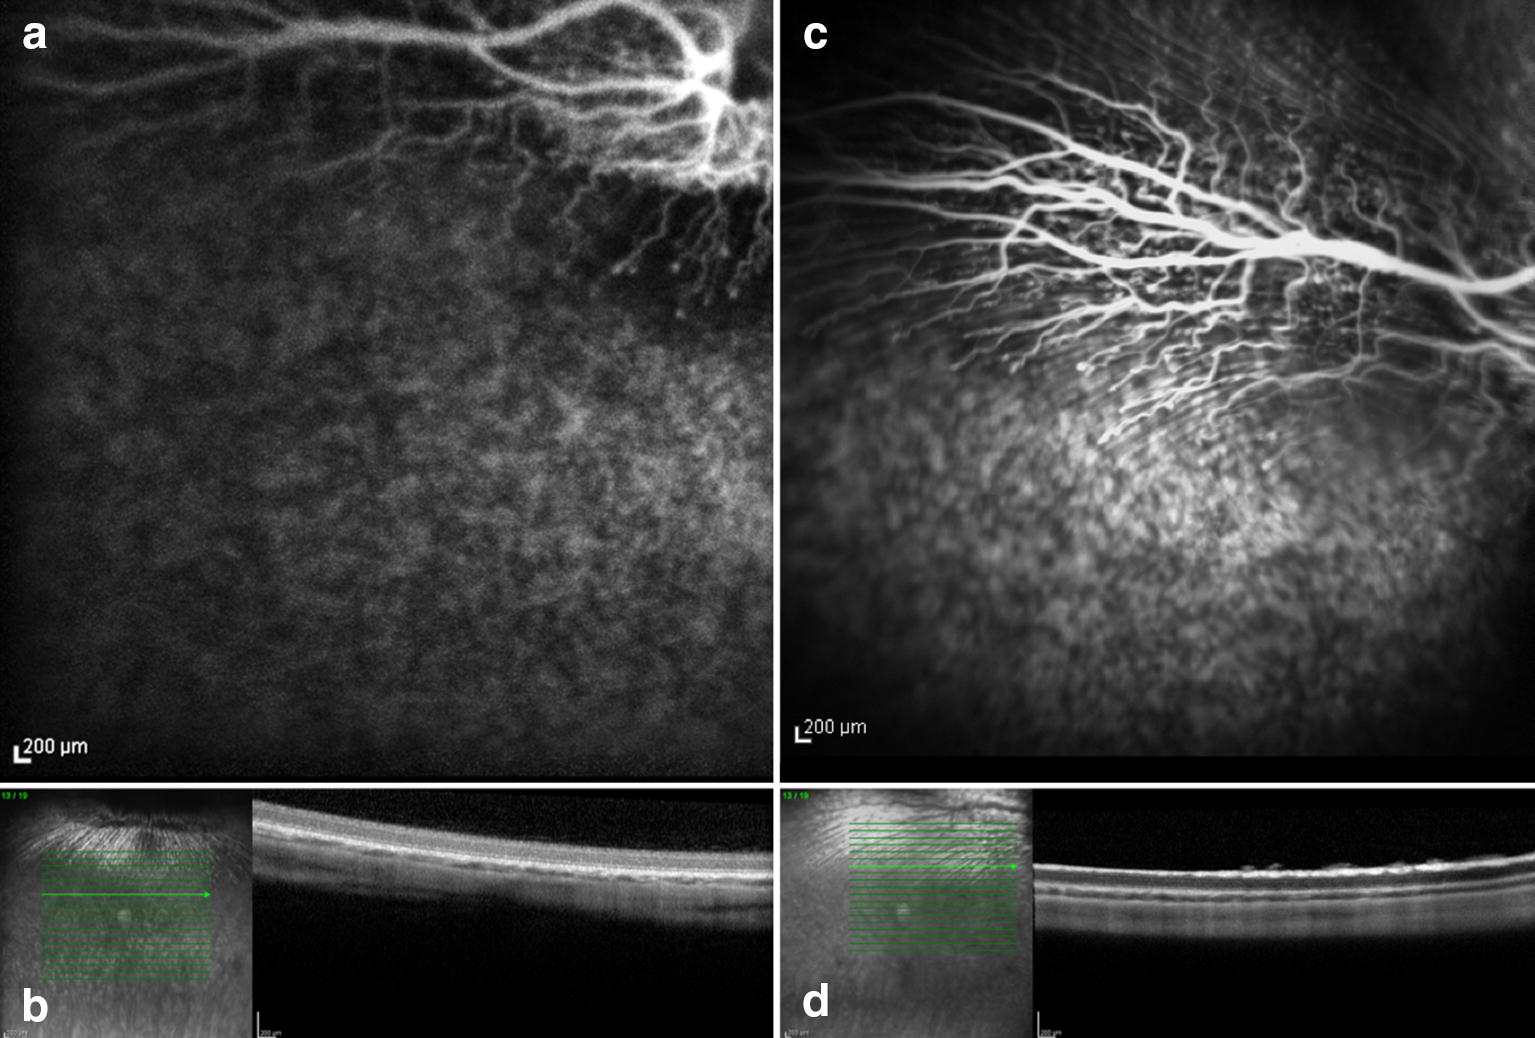

Fig. 2.

Preoperative and seven days posoperative fluorescein angiography and OCT. Rabbit (no. 1) exposed to 420 nm illumination after systemic administration of lutein. Postoperative hyperfluorescence corresponds to the exposed area and increased reflective of the inner and outer layers of the retina seen on OCT